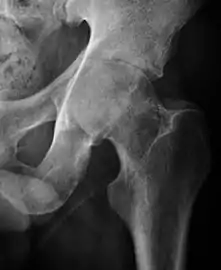

Plain radiography allows us to categorize the hip as normal or dysplastic or with impingement signs (pincer, cam, or a combination of both). Besides these, pathologic processes like osteoarthritis, inflammatory diseases, infection, or tumors can also be identified (Figure 1).[1]

Figure 1.

Radiography in normal hip

X-ray in pincer impingement type of hip dysplasia

X-ray of cam

Hip in osteoarthritis

Septic arthritis

X-ray in pediatrics